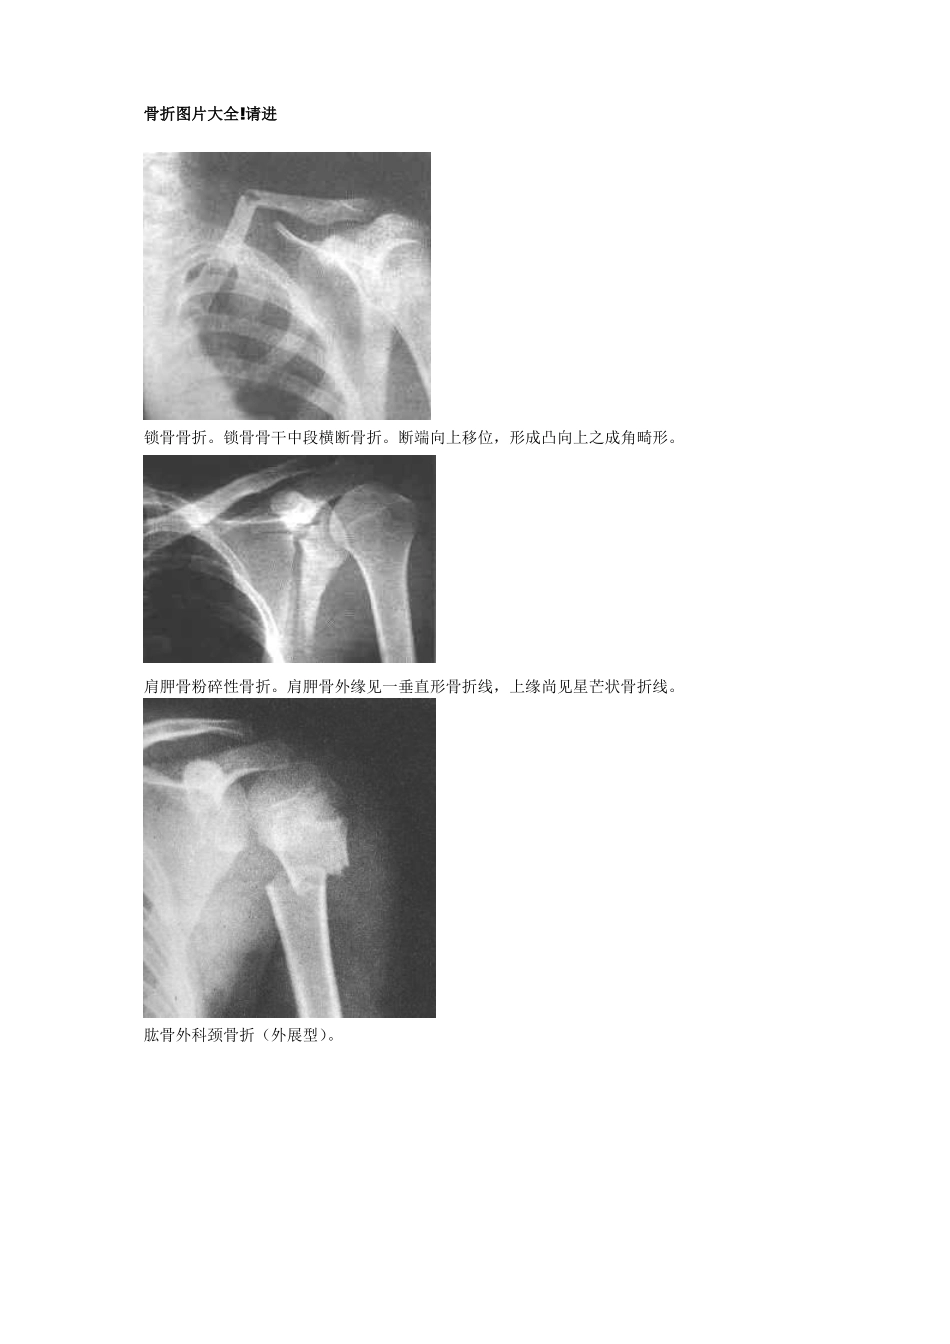

骨折图片大全!请进锁骨骨折。锁骨骨干中段横断骨折。断端向上移位,形成凸向上之成角畸形。肩胛骨粉碎性骨折。肩胛骨外缘见一垂直形骨折线,上缘尚见星芒状骨折线。肱骨外科颈骨折(外展型)。肱骨骨干骨折。远侧断骨向上外方移位,附近有小碎骨片。肱骨髁上骨折。骨折线呈不规则横形,远端骨片稍向掌侧移位。肱骨内侧髁骨骺分离。肱骨外髁骨折。肱骨外髁骨折片向外移位并翻转。孟氏骨折(伸直型)。尺骨骨折,近侧断骨指向前方和桡侧。与远侧断骨和桡骨成角。桡骨头向前外脱位。盖氏骨折。桡骨中下1/3骨折,伴远端尺桡关节脱位和尺骨茎突骨折。柯雷氏骨折。桡骨下端横形骨折,远端断骨向背侧倾斜移位,侧位片呈“匙”样畸形,伴尺骨茎突骨折。史密斯骨折。腕舟骨骨折。腕舟骨中部可见透亮线。第一掌骨基底部骨折。下肢骨折图片股骨颈骨折腓骨下段螺旋形骨折并踝关节半脱位胫骨下段斜形骨折尾指近-中节骨粉碎性骨折并完全性脱位跟骨骨折图片